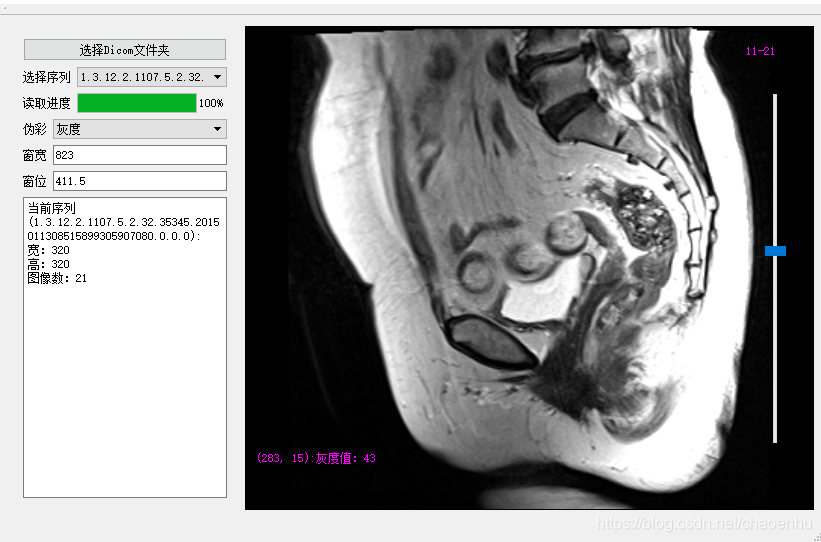

...运行调试,点击“选择Dicom文件夹”后

设置伪彩色

调整窗宽窗位:1)通过按住拖动鼠标右键;2) 修改窗宽窗位值;3) 按住鼠标左键划框(感兴趣区域);